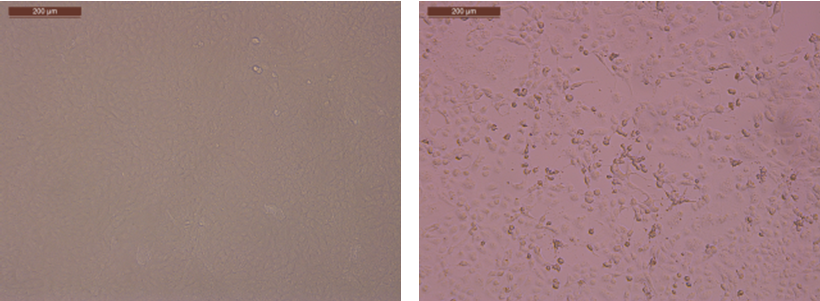

图1.病毒致细胞病变

左:细胞对照

右:nCoV-2019-28#

研究团队应用Vero E6细胞,成功分离出2019-nCoV毒株。目前已完成病毒的全基因组测序及病毒学鉴定工作。